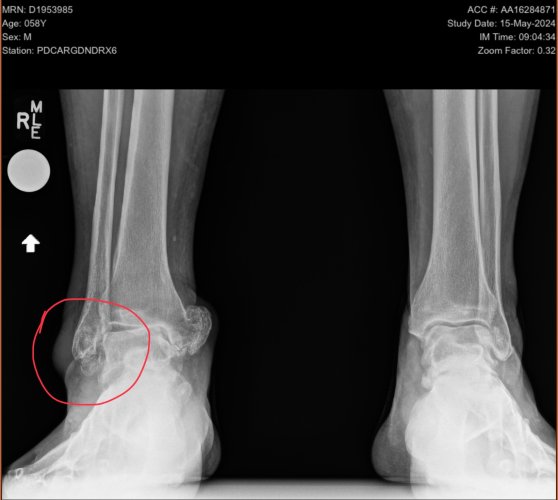

I’ve broken both of mine playing hockey. Left was about midway up, minor spiral fracture from crashing into the boards in an awkward position. That one healed up pretty easily.

Right was from a puck impact that broke the end completely off. That ankle already had major issues and has now been completely replaced. Recovery from that has been quite a bit more challenging.

IMG_0511.jpegIMG_0512.jpeg